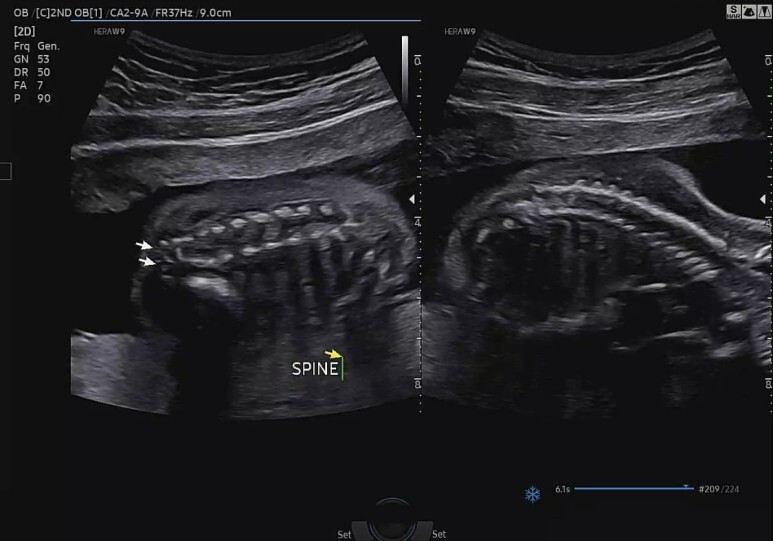

척추뼈 확인(SPINE)